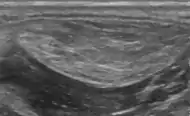

التصوير بالموجات فوق الصوتية الطبية للورم الشحمي في سماحة الرانفة: إنه منخفض الحرارة مقارنةً بالعضلات المجاورة، ومعرف جيدًا نسبيًا، مع خطوط فرط تصبغية مصغرة. [13]